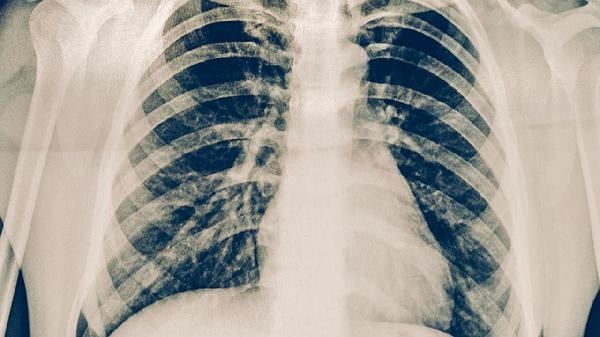

肺結(jié)核早期可能出現(xiàn)低熱、乏力、盜汗等癥狀,隨著病情進(jìn)展可表現(xiàn)為咳嗽、咳痰、咯血等。肺結(jié)核是由結(jié)核分枝桿菌感染引起的慢性傳染病,主要通過呼吸道傳播,常見癥狀主要有持續(xù)咳嗽、午后低熱、夜間盜汗、體重下降、胸痛等。若出現(xiàn)疑似癥狀,建議及時(shí)就醫(yī)進(jìn)行痰涂片、胸部X線等檢查。

病變累及胸膜時(shí)可出現(xiàn)針刺樣胸痛,咳嗽或深呼吸時(shí)加重。胸痛多提示結(jié)核性胸膜炎或肺部病灶靠近胸膜,可能伴隨呼吸困難。需通過胸部CT明確病變范圍,治療可聯(lián)合使用對氨基水楊酸異煙肼片等二線藥物,疼痛明顯時(shí)可短期使用布洛芬緩釋膠囊緩解癥狀。